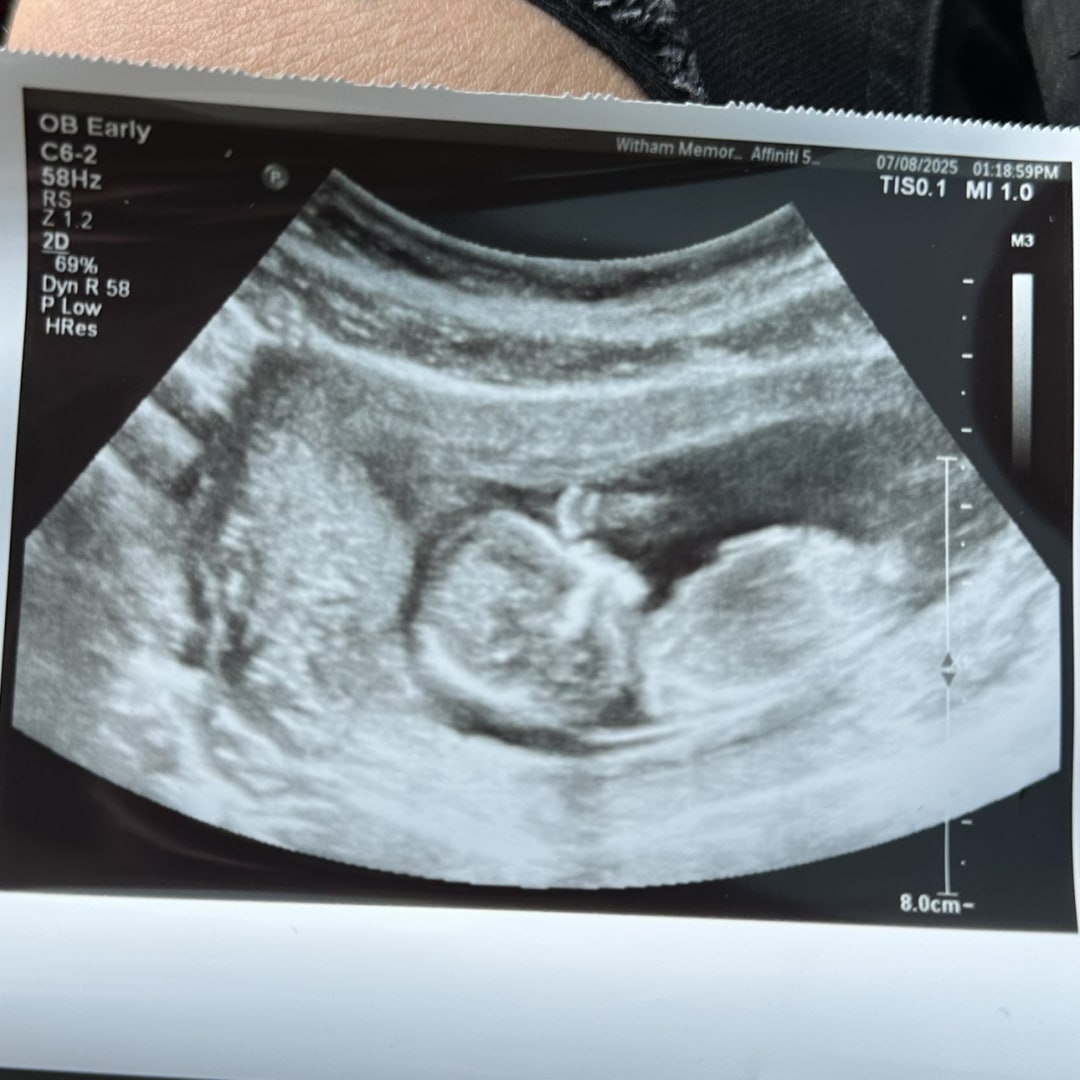

Rainbow Baby GIRL Hayes arriving in January. Thank you for everyone using our registry! We appreciate you all so much! 💕